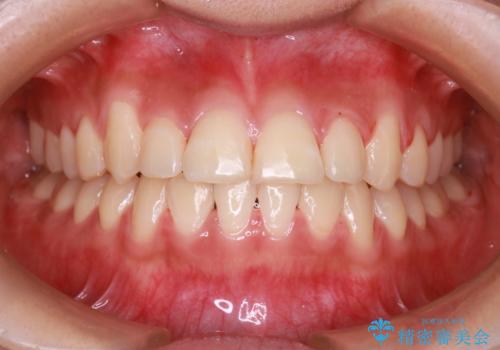

装着時間に不安がある人は、ワイヤー矯正をおすすめしております。短期間で治療でき患者様にも満足していただきました。